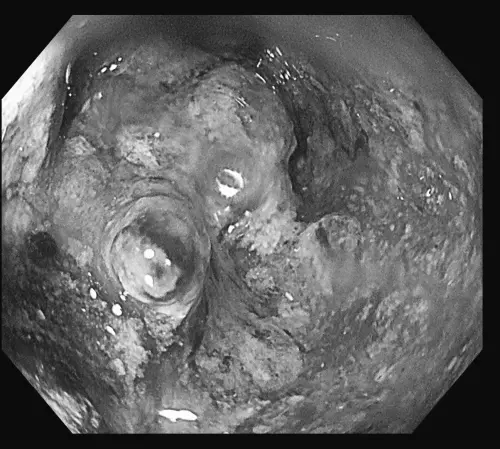

▲醫師透過大腸鏡檢查發現,腫瘤幾乎塞住整條腸道,正是患者⻑期血便與腹痛的主因。(圖/禾馨醫療提供) 事實上,政府早已提供方便的篩檢資源。符合資格的⺠眾(45 至 74 歲,或 40 至 44 歲有家族病史 者),每兩年可享有一次免費的糞便潛血檢查。林相宏指出,這項檢查只需要把糞便樣本交給健保特約院所,就能知道腸道是否有出血風險,及早安排大腸鏡檢查。對比動輒數十萬元的治療費用,篩檢不但免費,更可能救你一命。